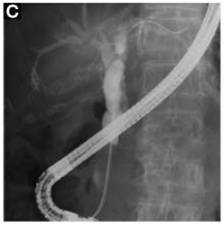

⑥ERCP

内镜下逆行胰胆管造影术(ERCP)指在内镜下经十二指肠乳头插管注入造影剂,做胆胰管X线造影胆汁细菌学和细胞学、胆道压力及乳头括约肌功能测定等检查,是公认的诊断胰胆管疾病的金标准。在ERCP的基础上可作十二指肠乳头括约肌切开术 、胆胰管碎石取石术 、胆胰管内支架安置引流术 、 鼻胆引流术及胆道蛔虫取出术等治疗。我院消化内科开展ERCP、EST等内镜 微创技术多年,至今已经完成多例胆道结石、蛔 虫、肿瘤、先天异常等疾病的的内镜诊疗,取得很好效果。

ERCP提示胆总管结石

切开乳头

取出结石

支架引流术

【内镜下十二指肠乳头括约肌切开取石术(EST)】

胆总管结石可引起急性化脓性胆管炎和急性胰腺炎,一旦诱发重症胆管炎或重症胰腺炎,死亡率很高,因此,该病应及时尽早治疗。胆总管结石的治疗方式很多,但以不开刀方式通过内镜经口腔进行取石—EST是目前最好的治疗方法。